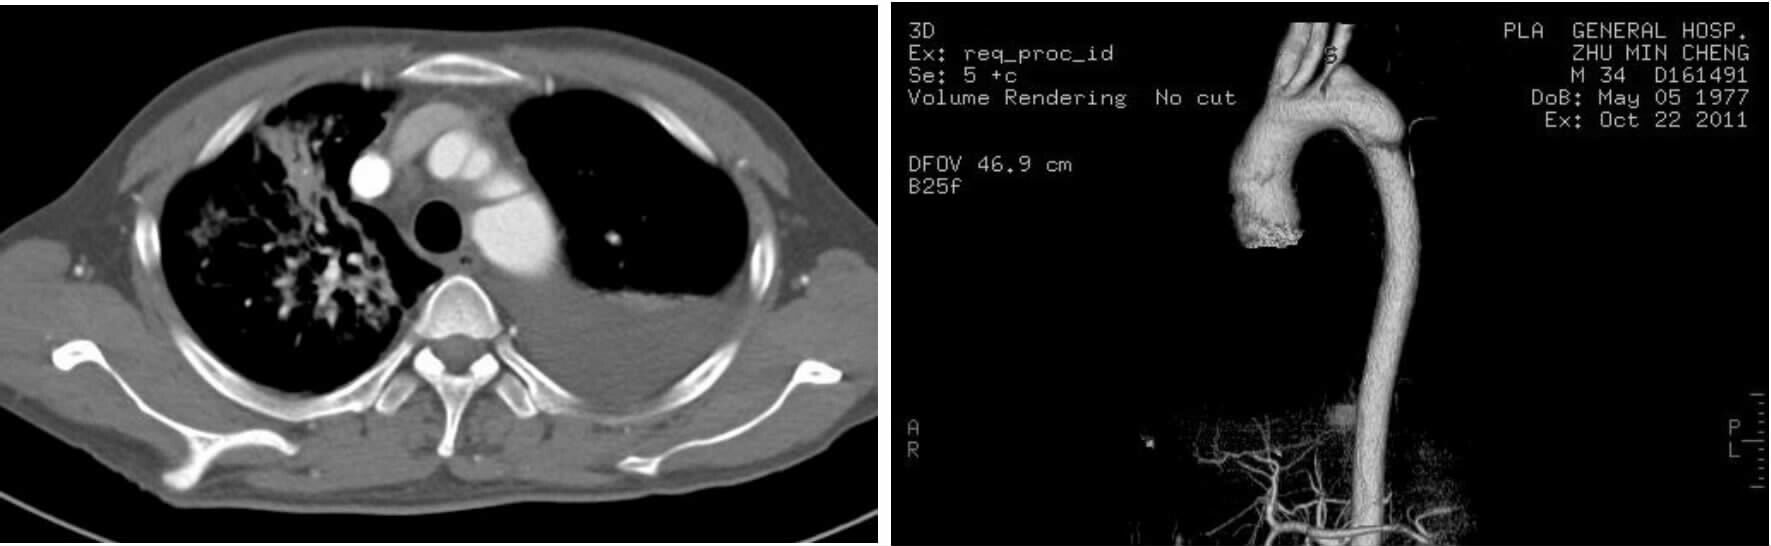

2 结果37例钝性胸主动脉损伤,CTA征象表现为内膜瓣、轮廓异常、血栓、动脉收缩、假性动脉瘤、主动脉夹层6种情况。①内膜瓣:内膜瓣为增强的主动脉管腔内可见一个或多个弧形弱化区(图 1)。②主动脉轮廓异常:表现为主动脉管壁或轮廓不规则,圆形的主动脉横切面发生变化,(图 2)。③假性动脉瘤:指主动脉壁破裂出血,形成主动脉壁外的血肿,主动脉管腔与不规则瘤腔结合处呈锐性边缘(单侧或双侧),(图 3)。④主动脉夹层:内膜片和主动脉真假两腔形成是诊断夹层动脉瘤的基本征象。内膜片将血管分为真假两个腔隙。增强早期真腔密度高于假腔,随时间延迟,假腔密度逐渐增高,假腔密度可等于或高于真腔,(图 4)。⑤动脉收缩表现为损伤节段主动动脉直径小于正常节段动脉直径(图 5)。⑥血栓;主动脉腔内息肉样低密度区(图 6)。本组37例钝性胸钝性胸主动脉损伤患者,CTA征象存在内膜瓣34例(91.8%),主动脉轮廓改变或腔异常37例(100%),动脉收缩17例(45.9%),主动脉夹层10例(27.0%),假性动脉瘤21例(56.7%),血栓1例(2.7%)。

| 图 3 主动脉峡部损伤假性动脉瘤征象,左锁骨下动脉分支受压 Figure 3 Pseudoaneurysm sign of aortic isthmus injury and compression of the left subclavian artery. |

| 图 4 主动脉降部损伤夹层征象 Figure 4 Dissection sign of descending aortic injury |

| 图 5 主动脉峡部收缩征象 Figure 5 Contraction signs of aortic isthmus injury |

| 图 6 主动脉降部损伤,表现为息肉样血栓征象 Figure 6 Polypoid thrombosis sign of descending aortic injury |

3.3 CTA诊断钝性胸主动脉损伤的直接征象在选择的这组病例中,手术或主动脉造影均证实存在钝性胸主动脉损伤。CTA显示钝性胸主动脉损伤的征象包括内膜瓣、轮廓改变、假性动脉瘤、主动脉夹层、主动脉收缩及血栓形成。上述CTA征象可提示钝性主动脉存在损伤,是诊断钝性胸主动脉损伤的重要依据,对钝性胸主动脉损伤具有定性诊断价值。在阅CTA片时,注意观察有无上述征象存在,及时诊断钝性胸主动脉损伤。